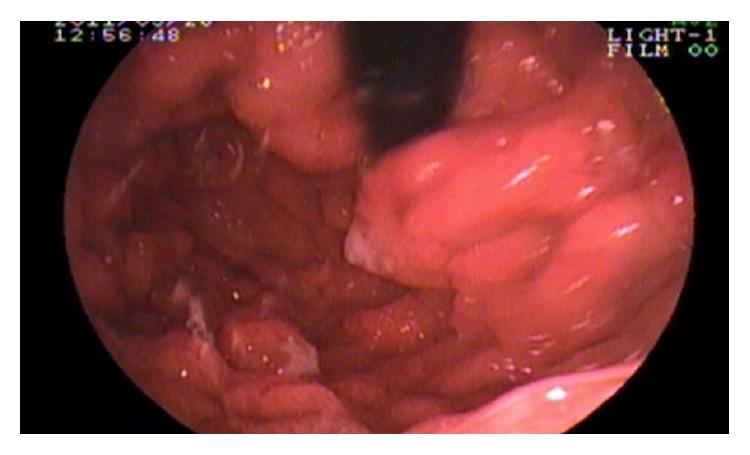

A young Indian man presented with nine-month history of chronic diarrhea, occasionally mixed with blood and intermittent colicky abdominal pain. He also complained of generalized body swelling for the last three months. On examination, he had diffuse hyperpigmentation of the skin and dystrophic nail changes. Upper and lower gastrointestinal endoscopy revealed multiple sessile polyps in the stomach, small bowel, and colon and rectum. Biopsy of polyps showed adenomatous changes with stromal edema and dilated glands. Cronkhite-Canada syndrome (CCS) was diagnosed and treated with glucocorticoids and enteral nutritional supplementation. There was an associated small intestinal bacterial overgrowth (SIBO) and stool was positive for clostridium difficile toxin. After 12 weeks of treatment, the patient achieved remission. Close correlation with clinical findings, including pertinent ectodermal abnormalities, endoscopic studies, and careful examination of biopsies will ensure a timely and correct diagnosis of CCS.

一名年轻的印度男性,有9个月的慢性腹泻病史,偶尔伴有便血及间歇性绞痛性腹痛。他还主诉在过去3个月全身肿胀。检查发现,他有皮肤弥漫性色素沉着及营养不良性指甲改变。上、下消化道内镜检查显示胃、小肠、结肠及直肠有多个无蒂息肉。息肉活检显示腺瘤样改变伴间质水肿及腺体扩张。诊断为克-卡综合征(CCS),给予糖皮质激素及肠内营养补充治疗。同时存在小肠细菌过度生长(SIBO),粪便艰难梭菌毒素检测呈阳性。治疗12周后,患者病情缓解。将临床发现,包括相关的外胚层异常、内镜检查结果以及仔细的活检检查紧密关联起来,将确保CCS得到及时、正确的诊断。